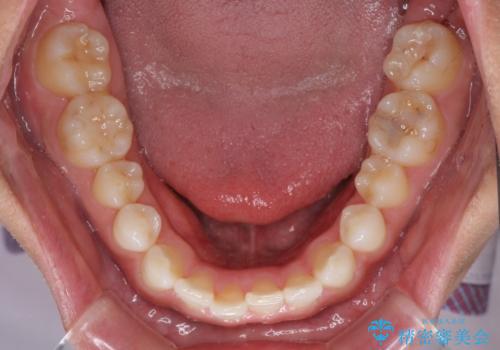

- 上下前歯のデコボコを気にして来院された患者様です。

以前矯正をした後戻りということで、歯列不正はそれほど大きくなかったため、インビザライン・ライトを用いて矯正治療を行うこととしました。

1日22時間以上しっかりと装着してくださったので、半年かからずに治療を終えることができました。